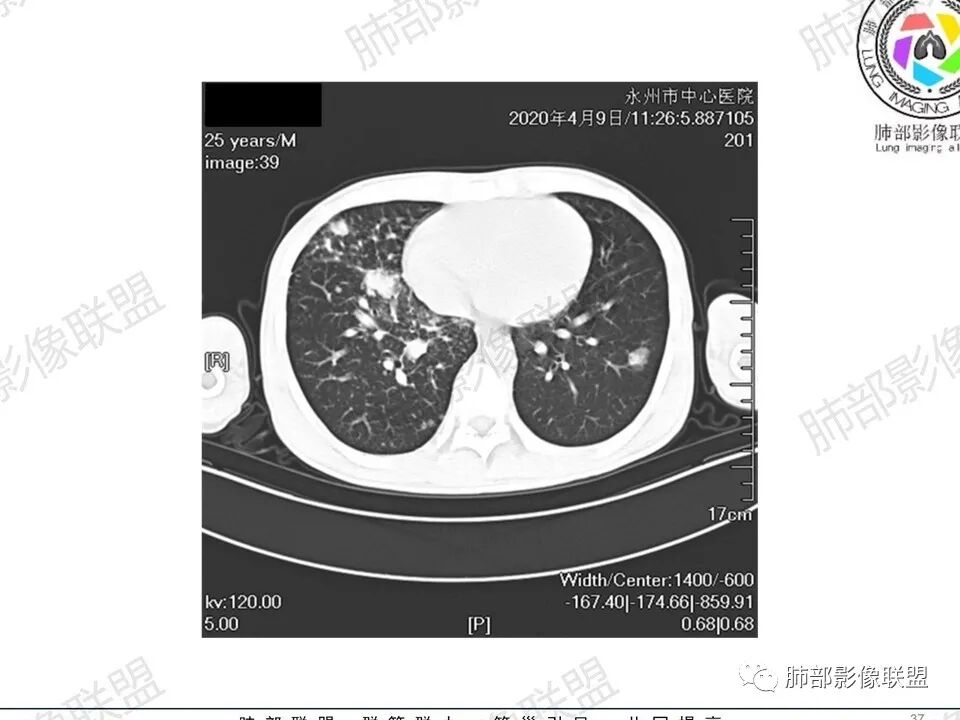

那个人:青年男性,慢性病程,咳嗽气促,伴盗汗胸痛。实验室,贫血,血沉快,C反应蛋白升高,低蛋白血症。影像,双肺散在斑片影,结节影,伴树芽,斑片影源支气管血管束分布,支气管走形自然,结节影有小空洞,有些周围有磨玻璃成分,小结节有些成串珠样改变,纵隔肺门淋巴结肿大,心腔低密度。考虑淋巴增值类疾病,结核?淋巴瘤?结节病?鉴别血管炎,实验室,影像不太支持

穿越七海的风:双肺多发结节斑片影,支气管通畅,间质浸润,纵隔肺门肿大淋巴结,考虑淋巴瘤?白血病浸润?结节病?

薏米:青年男性,慢性咳嗽,咳痰,气短,贫血,淋巴细胞低,尿隐血阴性,双肺散在多发结节,斑片,树芽影,支气管充气,肺门,纵隔淋巴结肿大,融合趋势,考虑淋巴瘤,鉴别结核

甄德强:年轻男性,慢性起病,双肺多发斑片影,结节影及粟粒点状影,纵隔及双肺门淋巴结肿大,似乎密度不均,结核中度症状,血沉快,一元论考虑结核,鉴别诊断结节病。

一切∮随缘:双肺多发大小不等结节,结节密度高,边缘清楚,部分结节内可见血管穿行,另右肺长条状实变影,内部可见支气管充气征,局部支气管壁增厚,双肺多发小树丫,双肺门及纵隔淋巴结肿大,部分融合,无增强,对淋巴结坏死无法判断,临床:年轻男性慢性病史急性加重,血象、CRP、ESR高,考虑一元论:结核(年龄加影像都符合),二元论:结节病或淋巴瘤+结核(建议CT增强及淋巴结穿刺),无原发肿瘤病史,癌性淋巴管炎代排。

刘L:纵隔多发淋巴结肿大,自肺门向上呈对称性分布,部分融合,内密度均匀;双肺散在分布大小不等结节,边界清晰,右肺中叶部分伴有实变,首先考虑结节病,建议增强扫描排除肺结核。

男性,25岁,咳嗽咳痰1年,气促两月,加重一天,伴盗汗胸痛。CT示双肺散在斑片影,结节影,树芽征,部分周围伴磨玻璃影,以右肺上叶明显,纵隔及双肺门可见多发淋巴结肿大,部分融合,青年人,病史较长,首先考虑结核,不排除结核合并结节病可能。

3、影像表现:双肺散在斑片影及结节影,部分结节内可见血管穿行,斑片影沿支气管血管束分布,近胸膜侧病变收缩不明显。部分中央淋巴间质增厚,小叶间隔增厚。病灶内支气管穿行,部分支气管略扩张。局部小结节呈串珠样改变。纵隔、肺门区、锁骨上及腋窝淋淋巴结肿大,部分有融合。心腔低密度。脾大。

2.双肺多发片影及结节影,边界可分辨,右肺中上叶较为密集,没有胸膜下分布优势。病灶实性密度为主,未见钙化及液化。

3.右肺较多微小结节,密度较为浅淡,部分沿血管束分布,未见沿小叶间隔及叶间裂分布结节影,未见典型的终末气道树芽。

4.病灶区域穿行支气管显示良好,未见壁增厚及管腔狭窄。

5.双肺门及纵隔淋巴结显著增大,这改变相当显眼。这里强调“双肺门”及“多发”!